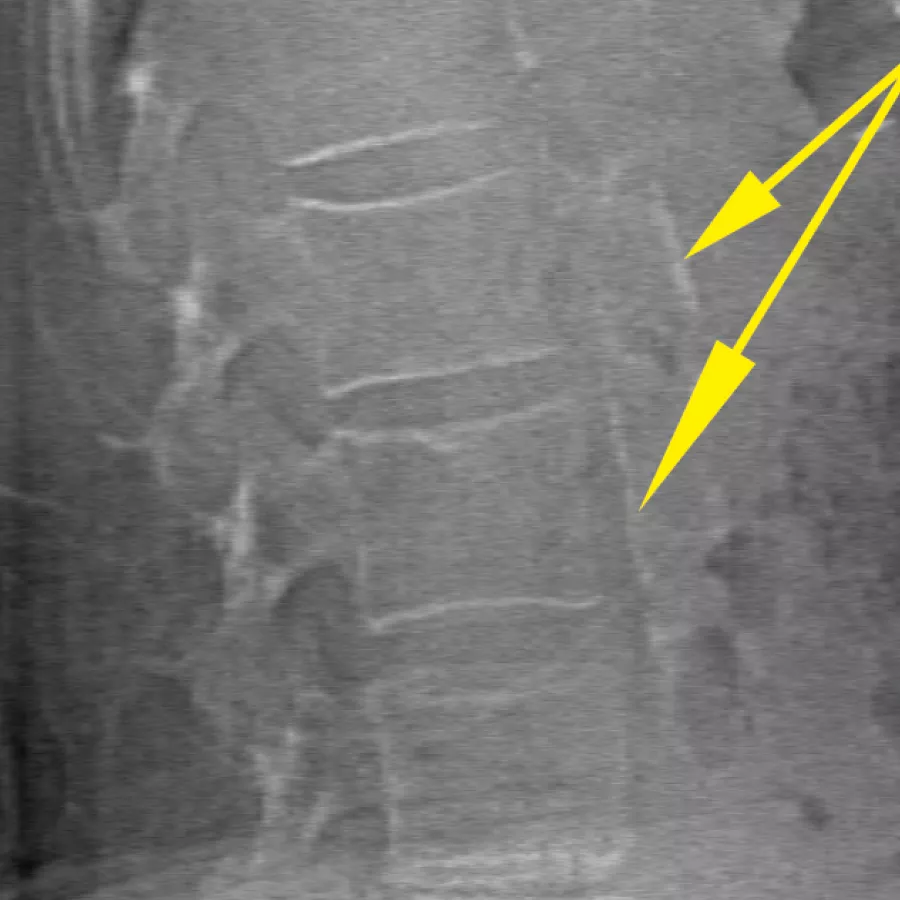

Avalie o risco de fratura através da combinação de uma medição precisa da densidade óssea com imagens vertebrais de alta resolução. É possível identificar fraturas da coluna vertebral com uma imagem de baixa dose e energia única em 10 segundos.

Melhore a precisão e reduza os erros de análise pós-exame com a colocação precisa e assistida por software de espaços entre os discos vertebrais para análise gráfica.

A funcionalidade MXApro™ no software operativo APEX™ classifica automaticamente a deformidade vertebral e comunica os dados diretamente à funcionalidade de diagnóstico integrada Physician's Report Writer™. Isto significa que pode acelerar o fluxo de trabalho através da interpretação integrada e remota sem a utilização de papel e gerar relatórios com um clique. Pode ainda visualizar e interpretar imagens e informações de qualquer local em qualquer dispositivo.